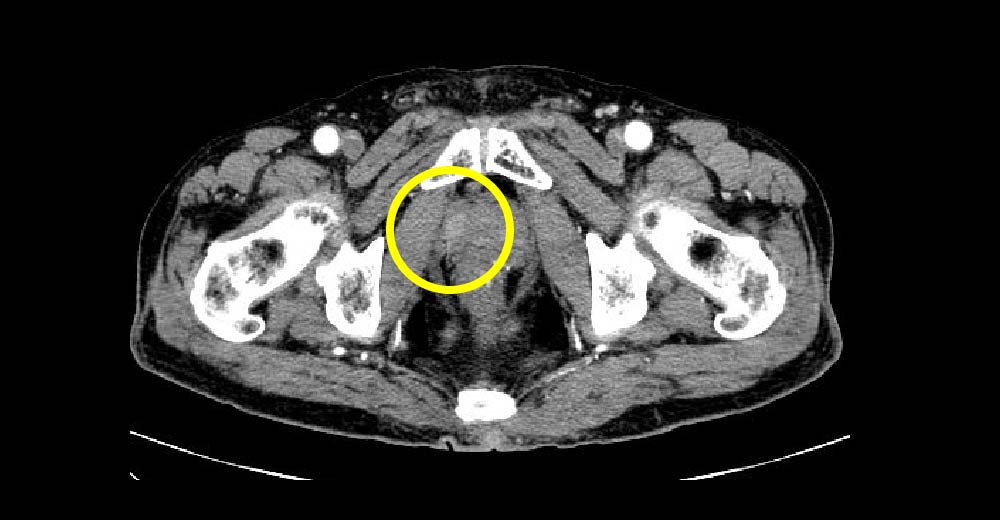

前立腺がん症例です。前立腺生検前にMRI撮影を行っています。

造影CTにて前立腺に造影効果のある高吸収域が指摘されます。

前立腺がん